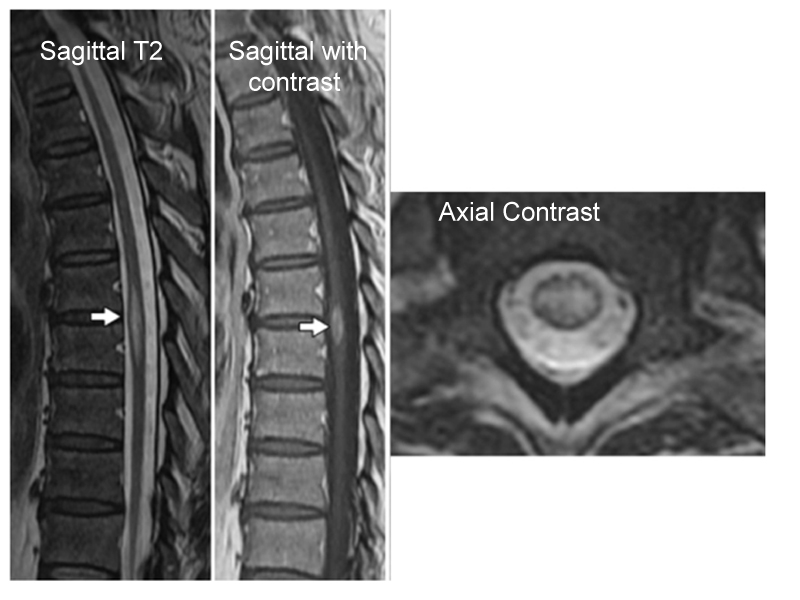

NMOSD MOG Ab Disease Sarcoidosis Paraneoplastic Dural AVF Cord Infarction Cervical Spondylosis